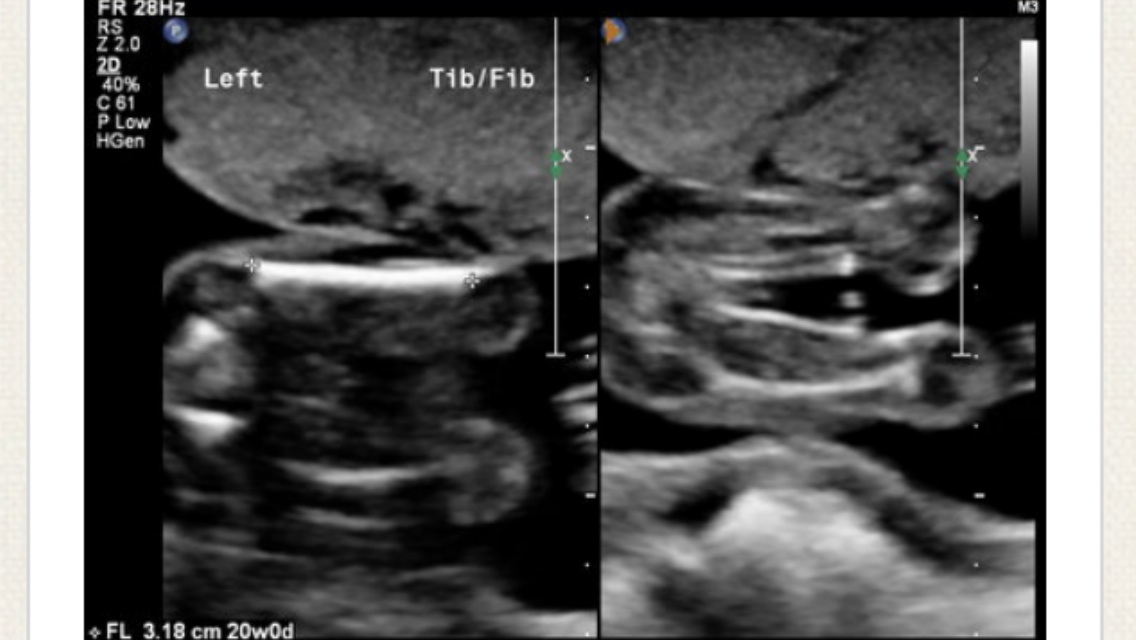

I can't tell of it's a pee pee or the chord?

Looks like a boy in the second pic, but it could be the cord?